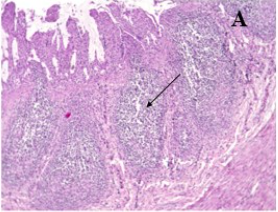

Kết luận: Các bệnh tích đại thể ở dạ dày, ruột gồm sung huyết, niêm mạc xuất huyết, chất chứa trong lòng ruột có mùi tanh máu. Bệnh tích vi thể rõ nhất ở ruột với nang lympho thành ruột tăng sinh, thoái hoá tế bào biểu mô, lông nhung đứt gãy. Bệnh tích của hạch lympho cho thấy số lượng bạch cầu lympho giảm mạnh ở vùng vỏ các nang hạch màng treo ruột; bạch cầu đơn nhân lớn và đại thực bào tăng mạnh. Các bệnh tích khác quan sát được gồm viêm kẽ phổi, viêm phế quản phổi và tăng sinh các vùng tuỷ trắng trong mô lách.

| Hình A. Nang lympho thành ruột tăng xinh (X100) | Hình B. Tế bào biểu mô ruột thoái hoá (X400) |